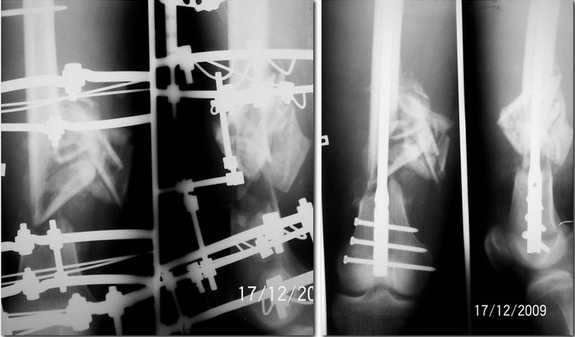

Re: застарелый открытый многооскольчатый перелом бедренной кости

послал Николов Олег 18 Декабрь 2009, 01:41

Прислушавшись к мнению уважаемых коллег провели двухэтапное лечение пациента. Пару дней

назад забили штифт, без укорочения, колено редрессировали до 90гр. Всем спасибо за дельные

советы.